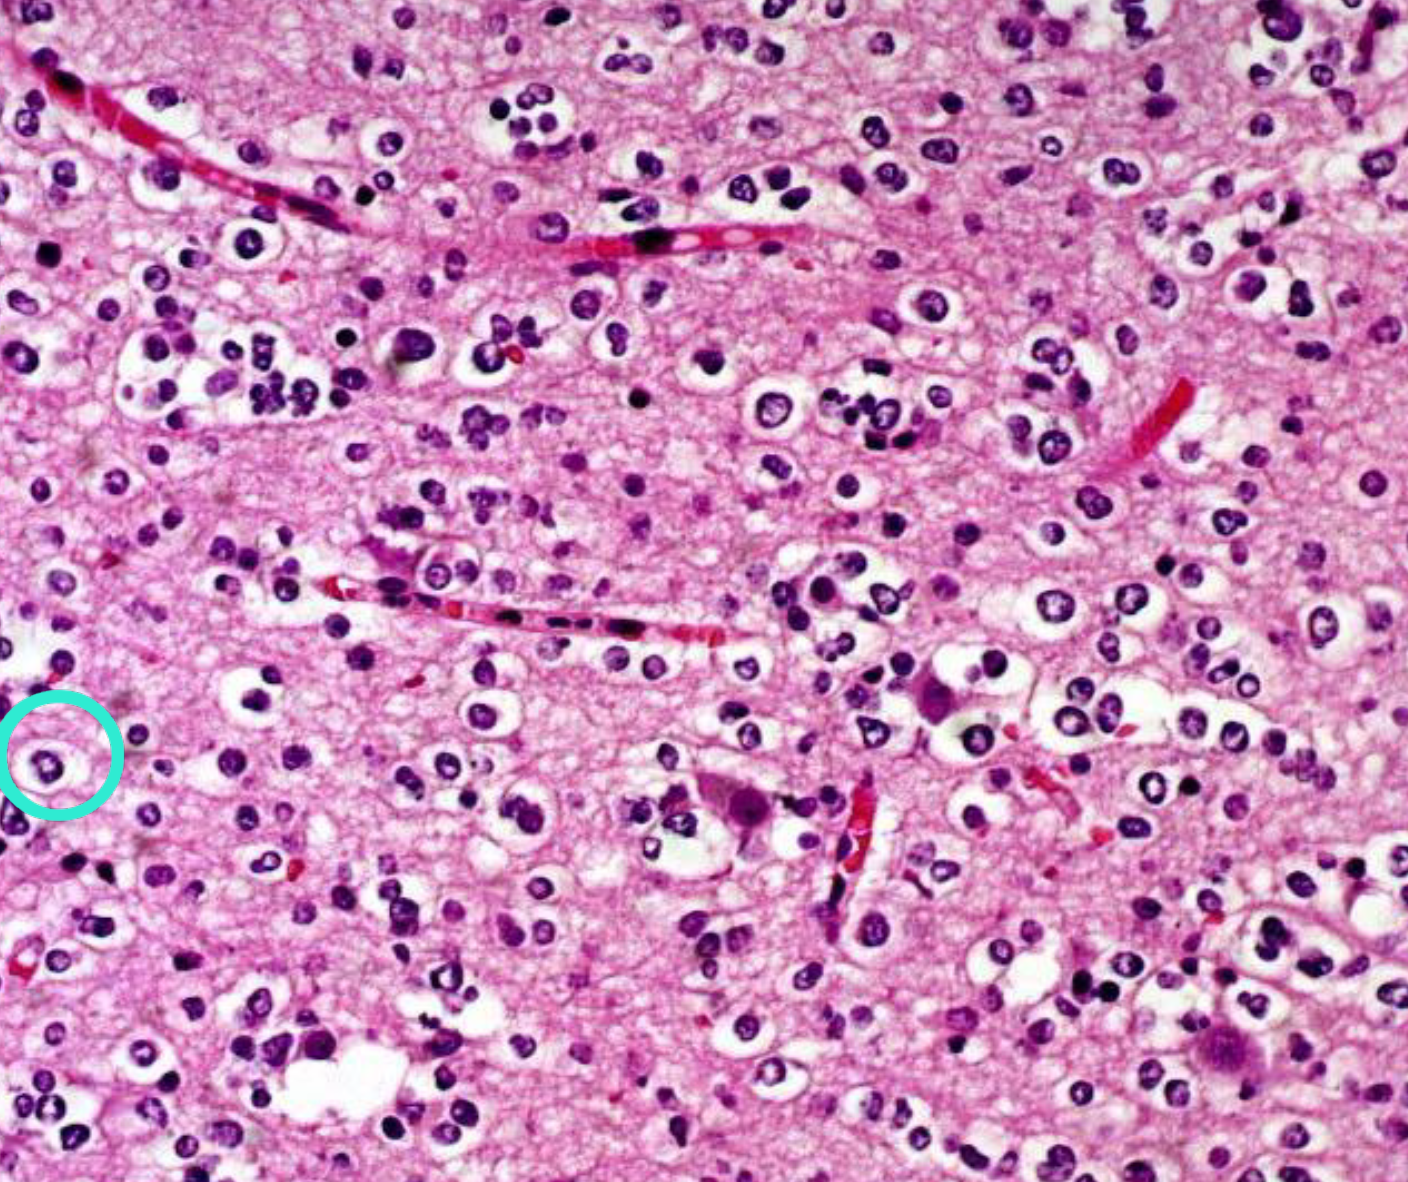

oligodendroglioma

- IDH-mutant, 1p/19q codeletion으로 진단한다. grade 2~3

- 계란프라이 모양과 맥아리 없는 혈관 모양이 특징적이다.